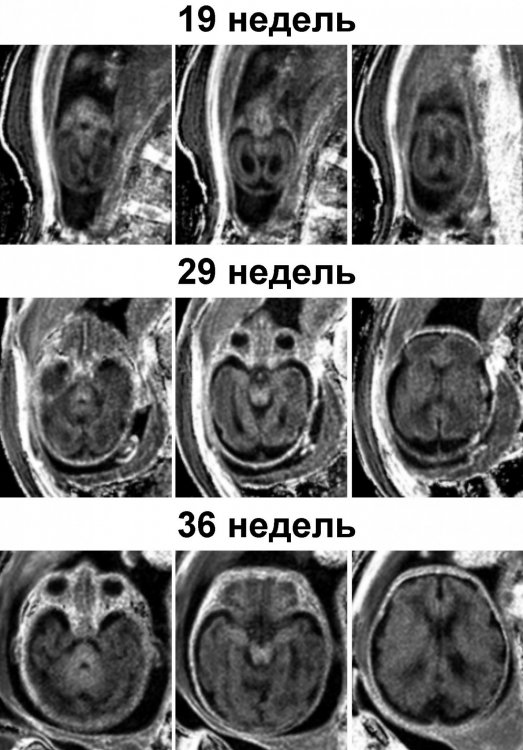

Поскольку в МТЦ СО РАН регулярно проводится МРТ плода, у исследователей уже были данные о возможностях количественной оценки внутриутробного развития мозга. Им стало интересно применить новый метод — чтобы изучить, как изменяется структура мозга в процессе его формирования, начиная от второго триместра до рождения ребенка.

Дело в том, что количество миелина у плода настолько минимально, а размеры отдельных структур головного мозга настолько малы, что любые количественные измерения очень сложны и трудоемки. К тому же ребенок в утробе постоянно шевелится, что сильно затрудняет получение качественных изображений. Нужен был способ, позволяющий делать снимки как можно быстрее и извлекать из них максимум информации. Именно таким оказался метод профессора Ярных, основанный на анализе содержания макромолекулярных протонов с помощью комбинации различных импульсных последовательностей и последующей математической реконструкцией количественных изображений.

Таким образом, с использованием 1,5Т томографа Philips на базе МТЦ СО РАН проведено уникальное исследование, показывающее, в каких структурах мозга и в какие периоды его развития начинает формироваться миелин.